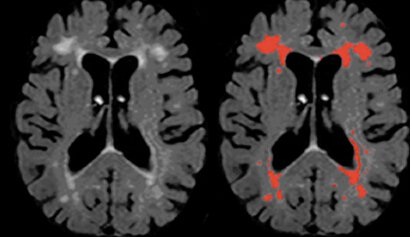

很多老年人会有这样的经历,因为头痛、头晕或其它症状去医院看病,做了头CT或者核磁(MRI),报告单上显示脑白质脱髓鞘改变,或者脑白质变性,多发腔隙性脑梗死等。很多人心中会有疑虑,这些到底是怎么形成的哪?是不是脑白质病变,医生所说的哪些小点点就是老年痴呆的前兆啊?我这就已经是脑梗死了么?是不是需要住院检查?其实影像上看到的是多种病因导致的结果,如长期高血压、糖尿病等危险因素或脑小血管病等导致的脑白质病变,区别于原发性的中枢神经系统脱髓鞘病,研究表明,部分脑白质病变与认知障碍存在一定的相关性,但并不是绝对会发展为痴呆。而腔隙性脑梗死属于脑梗死的一种特殊类型,多是高血压小动脉硬化引起的微梗死,少数病例可能由动脉粥样硬化导致的微栓塞引起。梗死灶的直径多为0.2-15mm,当坏死组织被消除后残留小囊腔。腔隙性脑梗死的症状取决于梗塞部位,表现为腔隙综合征,临床常见的包括:纯运动性轻偏瘫、构音障碍-手笨拙综合征、纯感觉性卒中和共济失调性轻偏瘫等。也有相当患者并无临床症状,往往由CT或MRI检查发现。

核磁显示的脑白质病变